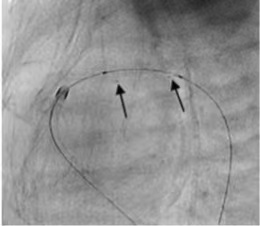

附:手术案例

成功应用IBS Angel™对动脉导管进行开通。术后即刻随访结果显示支架形态结构良好,患者动脉导管内血流通畅。